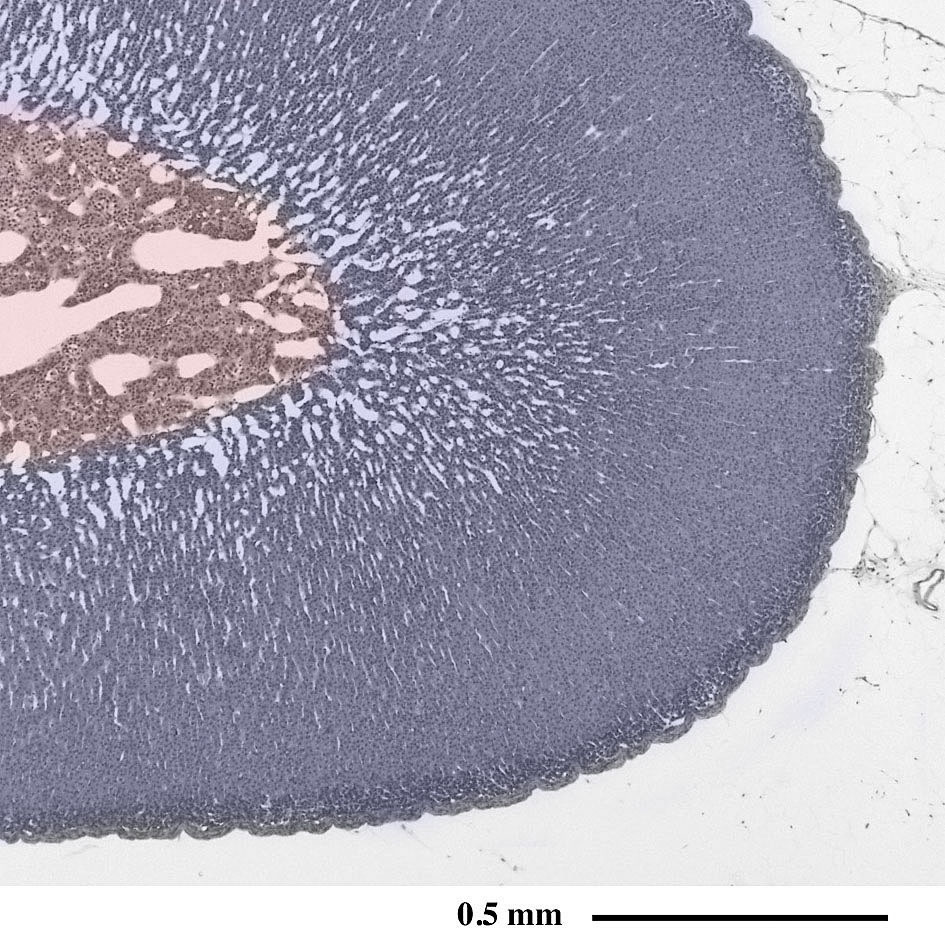

副 腎(ラット) Adrenal glands ( rat )

パラフィン切片のヘマトキシリン・エオジン染色光学顕微鏡画像

Light microscopic image of paraffin section with hematoxylin & eosin staining

副腎は腎臓の上部に位置する一対の内分泌器官です。内部は皮質と髄質に大別され、主に皮質からステロイドホルモン、髄質からはアドレナリンやノルアドレナリンが分泌されます。

副腎皮質(青)/副腎髄質(赤)